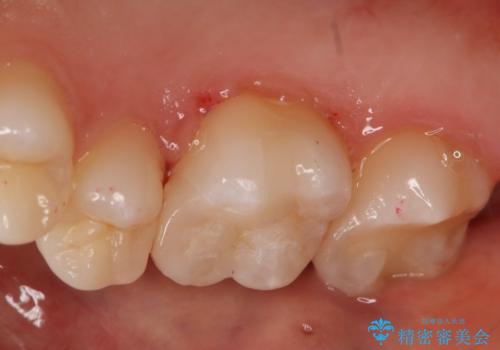

- 右上6番の保険材料で詰められた部分をセラミックにやり変え希望の患者様です。

切削量などを考慮し、セラミックインレーでの治療を選択しました。

う蝕が深くまで進行していたので、全て除去した上でCR裏層を行い形成、印象を行っています。